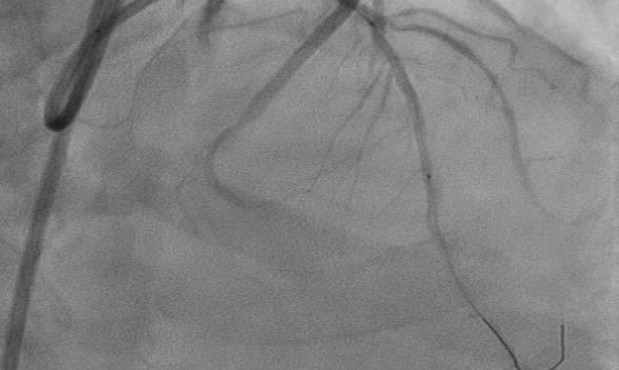

1) Proximal Left Anterior Descending artery's pre analysis done with OCT.2) Calcium arc on OCT displayed as 360 degrees with 800 micron thickness and length greater then 5mm with minimum Lumen Area of 1.83mm3) Intravascular Lithotripsy performed with focus on proximal Left Anterior Descending Artery4) Post Intravascular Lithotripsy procedure, Optical Coherence Tomography was performed5) The lumen gain obtained post procedure was equivalent to 5.24mm6) Stenting done7) LCX ostium with tight lesion with heavy calcification pre dilated with NC balloon and two stents placed.